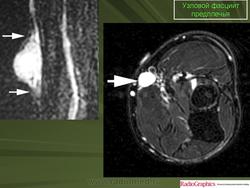

Узловой фасциит.

Нодулярный фасциит(син.: инфильтративный фасциит, узловатый фасциит, псевдосаркоматозный фиброматоз, нодозный фасциит, пролиферирующий фасциит, псевдосаркоматозная дерматофиброма) - самая частая узловая форма псевдосаркоматозной пролиферации реактивной природы. Развивается в глубоких слоях дермы, подкожной клетчатке, иногда в мышцах. У 10-15 % больных нодулярному фасцииту предшествует травма. Чаще болеют мужчины, преимущественно в возрасте 20-40 лет. До 20 % больных - дети. Локализация: голова, шея, ладонная поверхность предплечья, грудная клетка, спина, зоны по ходу периферических артерий и вен (у детей). В зависимости от локализации выделяют краниальный и внутрисосудистый фасциит, а также другие родственные формы фасциитов и миозитов.

Макроскопически нодулярный фасциитпредставляет собой нечетко отграниченный узел диаметром 1-5 см, на разрезе серовато-белый или пестрый, иногда с участками ослизнения. Не малигнизируется, рецидивирует крайне редко. Под микроскопом обнаруживаются многоклеточные, короткие или длинные пучки, состоящие из коллагеновых волокон и веретеновидных, иногда звездчатых фибробластов с вытянутыми ядрами. Пучки имеют S- или С-образную форму. Волокна внутри пучков могут иметь беспорядочную ориентацию или параллельное расположение. Встречаются муаровые структуры. В ядрах фибробластов хорошо видны ядрышки, можно найти фигуры митоза. Иногда обнаруживаются гигантские многоядерные клетки, налом инаюшие остеокласты. В связи с гистогенезом нодулярного фасциита из мио-фибробластов в клетках определяется экспрессия ряда «мезенхимальных» маркеров: с одной стороны, гладкомышечных антигенов - некоторых актинов (SMA и MSA), виментина и CD68 (КР1), с другой - кластера дифференцировки гистиоцитов CD56. Кроме того, в разных участках новообразования выявляются зоны ослизнения и мелкие кровоизлияния. В ряде случаев имеет место гиалиноз коллагеновых пучков. Нодуллярный фасциит следует отличать от пролиферативного фасциита, пролиферативного миозита, фибромы, фиброзной гистиоцитомы, нодулярного теносиновита, веретеноклеточной фибросаркомы.